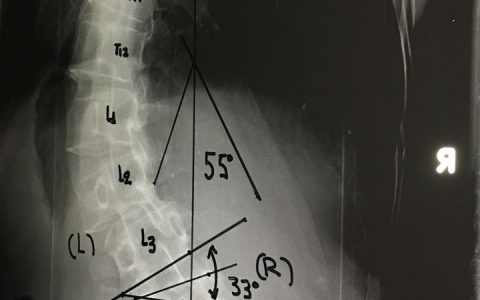

Περίπτωση : Κ.Ι. Κακοήθης Νεοπλασία Αυχενικής Μοίρας Σπονδυλικής Στήλης